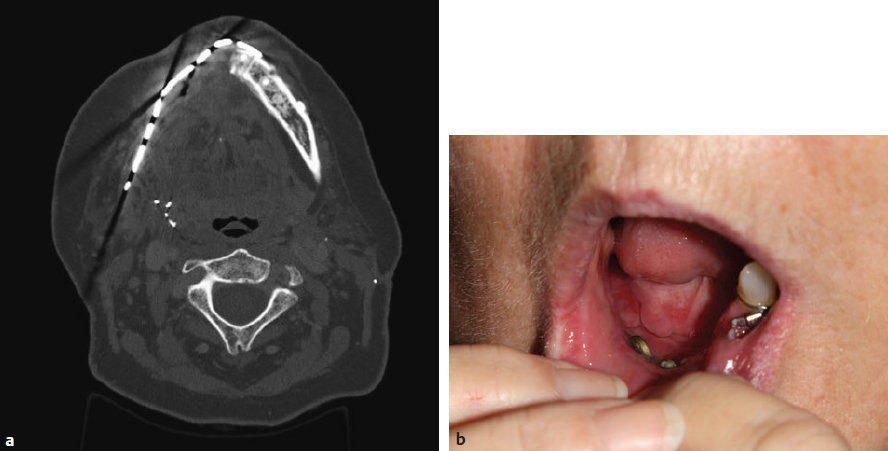

CHAPTER Restoration of the mandible and maxilla are among the most challenging and arduous procedures performed by reconstructive surgeons. Accuracy is paramount to restoring facial appearance and function, including airway maintenance, mastication, swallowing, speech, and, in the case of the maxilla, vision. This chapter focuses on reconstruction of segmental defects of the mandible and maxilla that require grafts and flaps for reconstruction rather than rigid fixation alone. An understanding of the nuances of reconstruction of this region of the body can help the surgeon achieve success in accurate reconstruction and minimize the chances for complications. Because microvascular free flaps play a huge role in contemporary mandibular and maxillary reconstruction, this chapter focuses on avoiding and treating complications related to free tissue transfer in addition to addressing other nonmicrovascular complications that are specific to these structures. Mandibular, and occasionally maxillary, reconstruction with a reconstruction plate that spans a segmental bony mandibular defect was a more popular technique before the development of microvascular free bone flaps. Some centers still rely, at least occasionally, on reconstructive plates when a patient is deemed unsuitable for a prolonged operative procedure involving free tissue transfer or when a surgeon with microvascular expertise is not available. However, experience has shown that such reconstructions are at high risk for complications, including plate fracture and exposure, either intraorally or through the skin of the cheek or chin. To help decrease the rate of exposure, many surgeons have attempted to combine reconstruction plates with a pectoralis major muscle or myocutaneous pedicled flap or a soft tissue free flap. However, Wei et al1 still reported a complication rate of 69% in patients undergoing mandibular reconstruction with a titanium plate and soft tissue free flap in a series of 80 patients. Plate exposure was the most common complication, followed by soft tissue deficiency, deformity of the lateral face, intraoral contracture, trismus, and osteoradionecrosis. Overall, complication rates associated with a reconstructive plate and soft tissue flap are reported to be between 21 and 87%.2 Anterior defects are associated with a higher rate of plate extrusion than lateral defects, as are defects in patients undergoing radiation treatment or with a history of prior irradiation. In addition, larger defects result in significantly higher failure rates than smaller defects. Even when patients are reasonable candidates for a free flap, some surgeons advocate plate or plate and soft tissue flap reconstruction in patients with advanced cancers and a limited life expectancy, because the surgery is usually shorter and recovery is usually faster. However, this approach must be carefully considered on a case-by-case basis, because the incidence of plate-related complications is high. In addition, the results are rarely ideal because of persistent contour deformity and malocclusion. Secondary salvage of such complications with vascularized bone flaps can be performed but tends to be more difficult than if it is performed at the time of the surgical resection. Additional difficulties at the secondary surgery include more challenging dissection of recipient vessels and greater difficulty restoring accurate occlusion because of postoperative and radiation therapy–associated scar contracture. Autologous bone grafts can be used for mandibular and maxillary reconstruction. The bone is revascularized by a process of creeping substitution. Sources of cortical bone graft include iliac crest, split calvarium, and rib. Nonvascularized bone grafts may be used in defects shorter than 5 cm. High failure rates are common in longer segments and in anterior defects. Preoperative or postoperative radiation therapy is usually considered a contraindication for mandibular reconstruction with bone grafts regardless of the size of the defect because of the heavy torque forces on the mandible associated with mastication. Therefore use of nonvascularized bone grafts for mandible reconstruction is usually restricted to patients with benign disease or who require mandibular surgery for posttraumatic or orthognathic rather than oncologic indications. Bone grafts can be used successfully in non–load-bearing parts of the maxilla and midface, such as in orbital reconstruction, but should be supported by well-vascularized tissues, such a pedicled temporalis or free flap, especially in the setting of irradiation. Microvascular free flaps are the preferred method of reconstruction for most segmental mandibular and maxillary oncologic defects. In particular, bone free flaps allow for restoration of facial contour, provide a stable surface for mastication, and, as long as there is adequate bone height and thickness, accommodate osseointegrated implants for dental restoration. Osteocutaneous free flaps not only replace mandibular or maxillary bone, but also are accompanied by a skin paddle that can be used to close soft tissue defects of the oral cavity and/or of the cheek and neck in the case of through-and-through defects. The most commonly used bony or osteocutaneous free flaps include the fibula, iliac crest (deep circumflex iliac artery), scapula, and radial forearm free flaps. Of these, the fibula osseous–osteocutaneous free flap is probably the most commonly used at most reconstructive centers. For specific defects, soft tissue free flap reconstruction alone without a reconstruction plate can give acceptable results for mandibular and maxillary reconstruction. An osteocutaneous free flap is necessary to maintain facial symmetry when there is an anterior defect of the mandible or maxilla.3–6 When there is an isolated posterior defect of the mandible or maxilla, a soft tissue free flap, such as the anterolateral thigh (ALT) or rectus abdominis myocutaneous (RAM) free flaps, can be used if the patient is not a good candidate for an osteocutaneous free flap (because of poor medical condition or peripheral vascular disease, for example).4,5 For the mandible, posterior defects that encompass the condyle, ramus, and as far anterior as the parasymphysis can be reconstructed with a soft tissue free flap. For such defects, the benefits of osteocutaneous free flap reconstruction are arguably less, because the aesthetic appearance is less affected by loss of bony structure, the muscles of mastication cannot generally be reattached in a functional manner, and there is no perfect substitute for the resected temporomandibular joint.7 There will be a tendency for mandibular de viation toward the side of the defect when reconstructed with a soft tissue flap alone that can be mitigated by slightly overcorrecting the volume of the defect with the flap. There is also a tendency toward flap atrophy, especially after radiation therapy, so a bulky flap can help improve the aesthetic result as well. Edentulous patients tend to have more deviation of the mandible, because they do not have teeth to guide their mandible into proper occlusion, which is another factor to consider when opting for a soft tissue free flap over an osteocutaneous free flap in posterior mandible reconstruction. In summary, osteocutaneous free flap reconstruction will tend to have better occlusal outcomes, but bulky soft tissue free flap reconstructions may be acceptable for patients who are not good candidates for an osteocutaneous free flap because of poor functional status, donor site unavailability, or limited life expectancy. For the maxilla, soft tissue free flaps or prosthetic obturators can be considered for defects posterior to the canine tooth.6,8–10 Defects of the posterior hard palate and alveolus can usually be reconstructed with soft tissue free flaps, such as the ALT or RAM free flaps (or the radial forearm fasciocutaneous free flap for obese individuals) with good functional and aesthetic results. It is important to make sure the flap is inset such that it is not ptotic into the oral cavity, because this makes concurrent use of a prosthetic for dental restoration difficult or impossible. For anterior defects, bony reconstruction is necessary to maintain midfacial height, width, and projection.11 Soft tissue free flaps can be combined with titanium mesh or bone grafts to reconstruct the orbital floor when the maxillary defect includes the orbital floor.6 In a review of orbital floor reconstruction for trauma, Kirby et al12 found that autologous bone reconstructions were more likely to be complicated by orbital dystopia and enophthalmos compared with titanium mesh and porous polyethylene, possibly related to increased difficulty in shaping the reconstructed orbital floor, irregular thickness, and unpredictable resorption. Because accurate reconstruction is very important to prevent these complications, as well as decreased vision or even blindness related to excessive pressure on the globe or the optic nerve, the orbit should be preplated with mesh before making osteotomies whenever possible. This mesh can then be used for the reconstruction or serves as a template for reconstruction with bone grafts. Alternatively, I am increasingly using three-dimensionally printed models to guide titanium mesh or bone graft reconstruction (Fig. 52.1). If the orbit is exenterated in combination with a superstructure maxillectomy that spares the alveolus and palate, soft tissue free flaps are usually indicated to obliterate the orbital cavity and close the orbito-sino-nasocutaneous wound.13 If the palate is also resected with the orbit and rest of the maxilla, a multipaddled soft tissue free flap is used to close both the intraoral wound and the orbital wound. Rarely, the defect is so extensive that the orbit and the anterior palate and alveolus are both resected. In such cases, our reconstructive algorithm would call for a soft tissue free flap to fill the orbital cavity and an osteocutaneous free flap to reconstruct the palate and alveolar arch to maintain midfacial projection. Fig. 52.1 A computer-generated model manufactured using three-dimensional printing technology assists the surgeon to reconstruct the left bony orbit by allowing complete visualization of the surgical defect in the absence of soft tissue structures that limit exposure so that hardware or bone grafts can be accurately shaped. Fig. 52.2 A pectoralis major myocutaneous flap used for cheek reconstruction. The flap has contracted inferiorly, causing a large wound dehiscence and, subsequently, a fistula. A palatal obturator is visible through the fistula. The base of the flap is bulky, and neck movement is limited. In patients who are poor candidates for a microvascular free flap reconstruction, the pectoralis major myocutaneous (PMMC) pedicled flap is sometimes used to reconstruct mandibular and maxillary defects.14 Use of this flap, alone or in combination with a titanium plate as described previously, should be considered a secondary option. Functional and aesthetic results are rarely optimal. Complications associated with using this flap include tethering by the proximal flap and vascular pedicle, restriction of neck movement and pulling of the bulk of the flap downward, an unsightly bulge in the neck, and, if adequate cutaneous perforators are not incorporated into the flap design, partial skin-paddle necrosis that can lead to a fistula (Fig. 52.2). If the PMMC flap is used, the skin paddle should be designed so that it is centered over the fourth intercostal space to provide adequate reach, and the proximal flap should be debulked as much as possible15 (Fig. 52.3). A long neck and short torso should be considered a potential contraindication for maxillary and even some mandibular reconstructions because of the inadequate reach of this flap. After major head and neck reconstruction, patients are usually kept sedated and on a ventilator overnight; they are weaned off the ventilator the next morning as tolerated, then transferred to a flap-monitoring floor when they are deemed stable. The advantage of having patients sedated overnight is it prevents unnecessary agitation and vomiting, which may result in an increased risk of hematoma or flap compromise. The disadvantage of keeping patients sedated and on a ventilator overnight is the need for high volumes of intravenous fluids because of the sedation and paralysis. Sedation and paralysis often cause hypotension and require intravenous fluid resuscitation, because vasopressors are generally considered contraindicated after free flap surgery. Therefore patients may become fluid overloaded, which can cause significant cardiopulmonary complications in patients with minimal cardiopulmonary reserve. In recent years, we have opted to allow some patients to breathe spontaneously without ventilator support and avoid sedation after surgery in our institution. These patients seem to recover faster and develop less cardiopulmonary complications with a shorter hospital stay. Venous thromboembolism, infection, and delirium tremens prophylaxis are given as indicated. Fig. 52.3 Maximal length of the pectoralis major myocutaneous flap can be obtained by centering the skin paddle over the interspace between the fourth and fifth ribs, where there are a number of myocutaneous perforators. Bulk in the neck and contracture of the flap can be minimized by making the base of the flap narrow, so that a minimum of muscle is included. Patients routinely receive tracheostomy and nasogastric feeding tube placement at the time of surgery. They then receive tube feedings for 2 weeks, while intraoral incisions are allowed to heal. For uncomplicated intraoral defects, a pureed diet is allowed after 2 weeks if all incisions appear to have healed without a fistula. For more complex defects, such those with a concurrent glossectomy, a modified barium swallow study is obtained to assess swallowing and to rule out a leak in areas that are not easily visualized by physical examination. Tracheostomy decannulation can usually be performed early, around postoperative day 5, when the immediate postoperative swelling has subsided. In select cases of maxillary reconstruction where the flap is not bulky and does not obstruct the airway, a tracheostomy is not performed, but the airway is closely monitored postoperatively in case the flap swells more than expected. Patients who undergo fibula free flap reconstruction are allowed to ambulate as early as postoperative day 2, even in a splint, with weight-bearing as tolerated on the affected limb.16 Early ambulation is important to prevent deep venous thrombosis and pulmonary complications. When not ambulating, the patient is instructed to keep the donor limb elevated at all times, whether in bed or in a chair, to facilitate wound and skin graft healing. We usually allow about 15 to 20 minutes of ambulation or dangling and advance gradually based on the amount of lower extremity swelling observed. When the orbit has been reconstructed, a forced duction test is performed at the end of surgery to rule out entrapment. Corticosteroids are given during surgery and again postoperatively if there is swelling to prevent pressure on the globe. If possible, the patient is woken up immediately after surgery rather than kept sedated so that the vision can be assessed. Visual checks are performed regularly in the postoperative period. Any decrease in vision is an indication for prompt ophthalmologic evaluation. Traumatic optic neuropathy secondary to traction injury is usually treated with high-dose steroids, and any impingement on the optic nerve or pressure on the globe should be relieved by emergent return to the operating room. Diplopia should be followed with computed tomography (CT) to rule out entrapment or suboptimal positioning of grafts and hardware used to reconstruct the orbit. Summary Box Complications Associated with Mandible and Maxilla Reconstruction Microvascular • Flap loss • Pedicle thrombosis • Venous thromboembolism Nonmicrovascular • Infection • Would dehiscence • Fistula Donor Site • Infection • Wound dehiscence • Skin graft loss (flap loss) • Lack of mobility and stability At our institution, trained nursing staff in a dedicated free flap unit perform hourly flap checks for the initial 48 hours and then every 2 hours for the next 48 hours, and finally every 4 hours until discharge. Any concern for a microvascular complication mandates immediate evaluation by a microsurgeon with a low threshold for operative exploration. The use of prophylactic anticoagulants such as heparin, dextran, aspirin, or low-molecular-weight heparin (i.e., enoxaparin) has not been demonstrated to improve flap survival or decrease pedicle thrombosis, and therefore the use of anticoagulants is not routine at our institution except as prophylaxis against venous thromboembolism.16 Signs of flap compromise such as increased swelling and bruising, change in color, or loss of the Doppler signal should prompt an immediate return to the operating room as long as the patient is medically stable. Early intervention remains the single most significant predictor of flap salvage, and, as such, a low threshold should exist for reoperation even at the slightest suspicion for thrombosis.17–19 A negative exploration is far preferable to a lost free flap. Every effort should be made to diagnose the cause of the flap compromise during reoperation (Fig. 52.4). Making the correct diagnosis is critical for salvage and prevention of future thrombotic events. Causes of flap compromise that can be corrected by clot removal and anastomotic revision performed in a timely manner include pedicle compression, kinking, or twisting; focal pedicle injury (e.g., those resulting from intimal injury near the anastomosis); and anastomotic error. Vein grafts are used as needed to replace sections of damaged pedicle or recipient vessel and relieve excess tension on the pedicle and anastomoses. Hypercoagulable conditions may also result in flap compromise and need to be addressed with anticoagulants after thrombectomy and anastomotic revision. Prolonged vasospasm or hypotension resulting in flap compromise are extremely rare and should be considered diagnoses of exclusion. They can be treated with topical vasodilators and by intravascular volume restoration, respectively. More problematic are thromboses related to purulent infection, traction injuries to the perforator(s) or distal pedicle, poor flap design, or injury to the distal circulation during flap harvest. These usually represent unsalvageable conditions. Although anticoagulant and antiplatelet medications are not routinely used as prophylactic agents, I do use them in select cases after a pedicle thrombosis not only if hypercoagulability is suspected but also if we are concerned about a residual clot in the distal microcirculation of the flap that could not be extracted during revision surgery. If return to the operating room is delayed or evidence of thrombosis of the distal flap circulation exists, I also use small doses of thrombolytics, such as tissue plasminogen activator (2–6 mg injected into the recipient artery with a 30-gauge needle or into a vessel side branch while the vein is clamped for several minutes to prevent dilution by release into the systemic circulation).16 However, in general, many of these interventions have not been demonstrated to have a significant impact on flap salvage.17 Fig. 52.5 (a) Computed tomography (axial view) of a right hemimandibulectomy performed for a mandibular ameloblastoma reconstructed with a titanium plate and pectoralis major muscle flap. (b) Intraoral exposure of the titanium plate that occurred several months after surgery. In most circumstances, reviving a free flap requires a lengthy operation, potentially additional donor site morbidity for harvest of vein grafts, added blood loss, need for blood transfusions, and a prolonged hospital stay and recovery. In certain circumstances, consideration should be given to abandoning a flap, immediately or after a judicious salvage attempt, and performing a second reconstruction rather than putting the patient through an extensive flap salvage operation, which may ultimately prove futile. We have demonstrated that delayed flap thromboses occurring later than 3 days after reconstruction and late recognition of flap compromise in which both the artery and vein are thrombosed are associated with significantly lower salvage rates. Similarly, compromised muscle-only flaps are also associated with worse salvage outcomes compared with fasciocutaneous and osteocutaneous free flaps. Multiple attempts at salvaging a failing free flap result in the most dismal prognosis and are not recommended.20 Before every attempt at salvaging a failing free flap, I discuss the possibility of abandoning the flap and performing an alternate reconstruction, either in the same setting or after a delay to wait for more optimal conditions in terms of the patient’s medical condition and the freshness of the surgical team. Ultimately, in the setting of a flap loss, the reconstructive microsurgeon is faced with a dilemma of whether to proceed with another free flap or pursue another option such as a pedicle flap or a prosthetic obturator (in the case of maxillectomy defects).6,21 In my experience, the loss of a free flap does not preclude the patient from another free flap provided that the patient is stable and medically able to undergo another free tissue transfer. For many mandibular and maxillary defects, if a free flap was indicated for the initial reconstruction, a free flap is still the best option in the setting of a flap loss and should be considered as the primary option if there are no definitive contraindications.22,23 Although a pedicled pectoralis major muscle or myocutaneous flap, with or without a titanium plate, represents a potential option in the setting of a free flap loss, at least for mandibular reconstruction, I usually prefer to use a second free flap, which has proven to be equally successful and demonstrates superior aesthetic and functional outcomes.21 Fig. 52.6 Coronal view of a computed tomography angiogram showing patent external iliac and deep circumflex iliac arteries bilaterally (arrows). Fig. 52.7 (a) Three-dimensional reconstruction of the iliac bone. Using computer-aided design (CAD) software, a right mandibular reconstruction has been planned. The planned iliac crest bone free flap is shown in light blue. The portion of the bone colored green will be removed and discarded. Use of CAD can be especially helpful when a prior resection has been performed and the original mandible is not present to use as a template for reconstruction. (b) A computer-generated cutting guide is used to help make osteotomies that duplicate the plan. Fig. 52.9 Postoperative appearance after iliac crest bone free flap reconstruction that demonstrated good facial symmetry. Patient management after a flap loss is to some extent dependent on identifying the cause of the flap, if possible, and taking the necessary steps to avoid the same conditions when performing a second flap. For example, if there is a suspicion for a hypercoagulable state, consideration should be given toward a hematology consult.21 The loss of a free flap used to reconstruct the mandible or maxilla because of infection or fistula (see later discussion) results in an inflamed, infected wound that may require antibiotics and serial débridement and washouts before another free flap reconstruction is done. When performing a second free flap, the surgeon and patient should be prepared for the use of alternate recipient vessels such as the transverse cervical vessels, contralateral neck vessels, internal mammary vessels, thoracoacromial vessels, or the cephalic vein and for the use of vein grafts.21,24 Particularly when a patient who is referred for reconstruction has lost a flap performed by another surgeon, I have found it useful to perform preoperative CT angiography of the potential flap vasculature to identify any abnormalities that may have caused the flap loss25–28 (Figs. 52.5 and 52.6). CT angiography of the neck may also be helpful in identifying available recipient blood vessels, especially when the prior surgery was performed by a different surgeon. Finally, in the setting of a delayed secondary reconstruction in which the original architecture of the mandible or maxilla is unknown, computer-aided design (CAD) of the reconstruction can be used to produce three-dimensional medical models, and computer-generated cutting guides can be invaluable in performing an accurate restoration27,28 (Figs. 52.7–52.9). In such cases, the fibula or other bony free flap can be shaped on the computer “virtually” so as to best restore facial shape and dental occlusion. Computer-generated cutting guides help the surgeon to make osteotomies such that the bony segments of the flap have the precise lengths and angles needed to replicate the preoperative plan made on the computer. Aside from complications associated with the microvascular anastomosis, patients undergoing free flap reconstruction are potentially at risk for a number of other complications. Often, patients undergoing major resections and reconstructive operations for extensive tumors are malnourished, have had prior radiation and chemotherapy, and have had a history of or may be actively using tobacco products. Consequently, these patients are potentially at risk for infection, wound dehiscence, and fistula formation during the perioperative recovery period. Although superficial infections can be managed with antibiotics, purulent deep space infections warrant prompt operative intervention. Early, aggressive drainage and irrigation of a neck abscess is critical to minimize the risk of a vascular rupture or flap loss. Infection can cause flap pedicle thrombosis, and, as mentioned previously, such cases of flap compromise are rarely, if ever, salvageable. Although minor wound separation can be managed conservatively, exposure of blood vessels, bone, or hardware warrants further surgery. In the setting of prior radiation and surgery, preemptive replacement of damaged neck skin with external flap coverage should be considered. Designing a flap with two independent skin paddles based on independent perforating blood vessels, or a chimeric flap with a skin and muscle component in which the muscle can be skin grafted, to separately close intraoral and extraoral defects obviates suturing radiated tissue together and may minimize the risk of wound dehiscence (Fig. 52.10). When this is not possible, a second free flap or a pedicled PMMC can be used for neck coverage (Fig. 52.11). Late complications include trismus and hardware failure. Trismus may be related to fibrosis of the temporomandibular joint (TMJ) secondary to radiation therapy or to cicatricial contracture of the skin paddle in some cases. TMJ fibrosis is usually treated conservatively with physiotherapy but is unfortunately often recalcitrant and may interfere with eating and dental care and restoration. Early and dedi cated prevention with mouth-opening exercises is critical to maintaining long-term function. Cicatricial trismus is often more easily treated with scar release and intraoral z-plasty or, when severe, an additional cutaneous free flap, such as the radial forearm flap. Hardware failure is very rare because of excellent bony healing of free flap tissues, but radiated bone may necessitate a new free flap (Figs. 52.12–52.14). Another promising development is the availability of computer-planned, custom-made titanium plates. Such plates are milled from a solid block of titanium and, because they have never been bent, are much stronger than traditional plates, but they also have a very low profile, which helps prevent plate exposure through radiated skin. The development of an orocutaneous fistula is often a major complication that can potentially lead to flap failure or death if a patient suffers a carotid blowout. A high index of suspicion should be exercised in all patients who have received preoperative radiation, chemotherapy, and surgery. Prolonged swelling, increasing erythema, malodorous or purulent discharge, or changes in drain output should all prompt further evaluation. Patients may or may not exhibit leukocytosis and fever. CT or a barium swallow may be indicated to evaluate for the possibility of a fistula but are not required for an obvious fistula. Early exploration is almost always warranted, because free flap pedicle thrombosis secondary to infection is almost never salvageable. A so-called “herald bleed” should be considered an emergency that warrants urgent exploration to prevent a life-threatening complication. Before neck exploration, irrigation, and débridement, the potential risks for multiple surgeries, prolonged wound care, and a flap loss should be explained to the patient. Empiric antibiotics are given and wound cultures are obtained at the time of neck exploration. Antibiotics are adjusted as indicated by the results of the wound culture. Based on experience, I manage fistulas with repeated operative or bedside irrigation and débridement procedures until the wound is clean. If the free flap has been lost, a second free flap is performed only when the wound is clean, because performing a free flap in a grossly infected field is associated with an increased risk of failure. Orocutaneous fistula reconstruction is usually performed with a pectoralis major muscle or myocutaneous flap, because attempts to close the fistula in the acute stage when tissues are inflamed are usually unsuccessful. In some cases, small fistulas that do not come in contact with the carotid artery or internal jugular vein, as well as a free flap pedicle or hardware, can be managed conservatively and allowed to heal on their own.